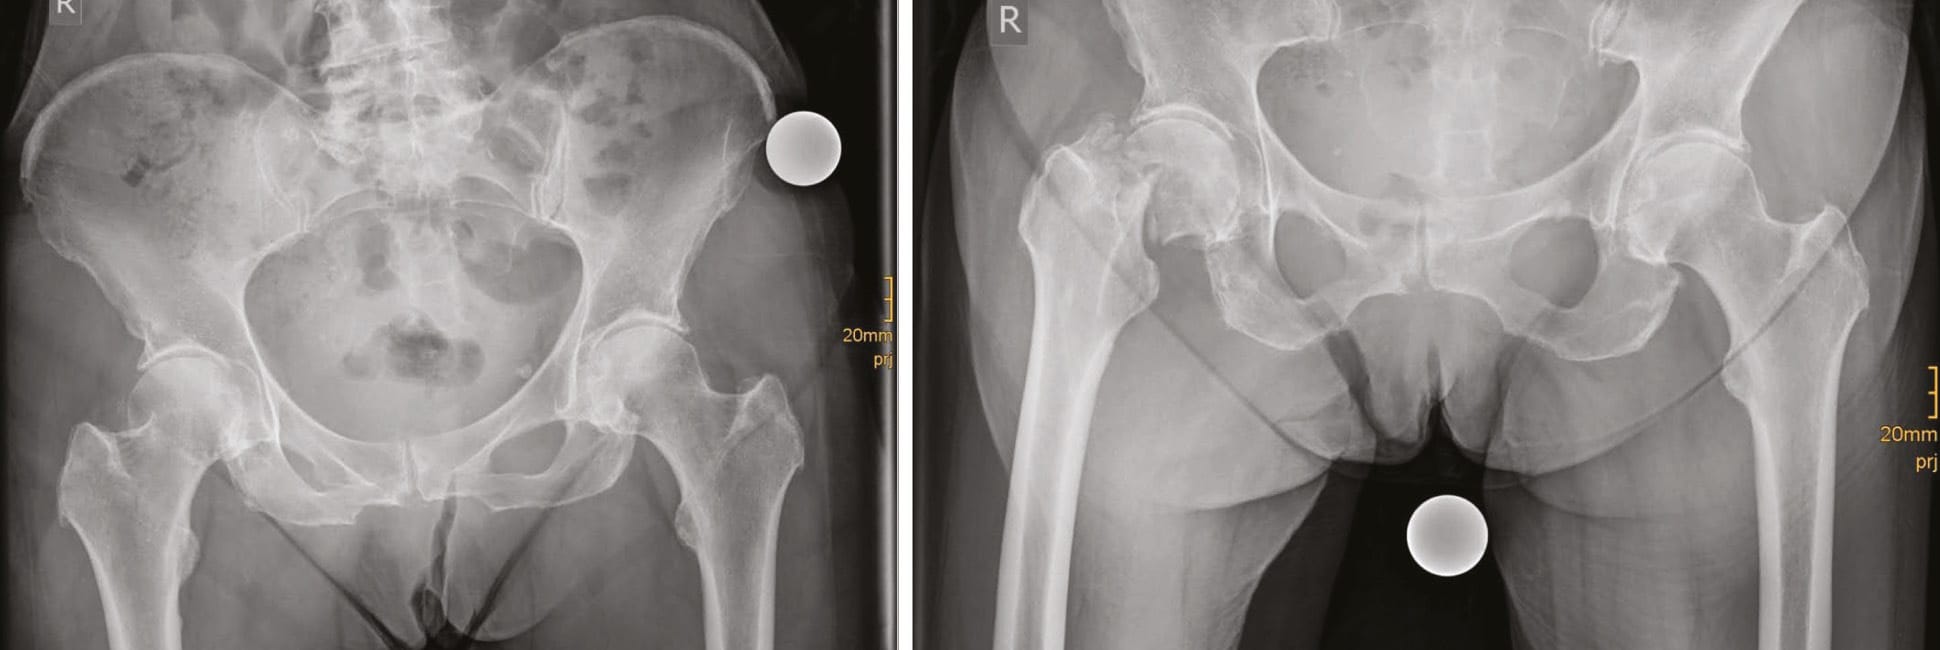

Conservative treatment remains an option, but only a small number of patients are eligible. Secondary dislocation can occur in up to 50% (Figure 3). In younger patients (<65 years) osteosynthesis with a DHS is our preferred method (Figure 2). In patients >65 years we prefer joint replacement even in undisplaced fractures (Garden I + II). Therefore the majority of our cases is treated with joint replacement procedures (Table 1.).

Hemiarthroplasty (HA) with 37% is still widely used. However, 57% of our patients obtain a THA. Cemented fixation is necessary in most cases due to bone quality, intraoperative cortical ring structure or known osteoporosis in the patient history. In active patients with good bone quality, femoral Dorr type A or B, intact cortical ring cementless fixation is possible. If cementless fixation is considered short stem fixation is possible and our favoured method. Straight cementless stems are rarely used. Our clinical and radiographic results using cementless short stems so far are very promising (Figure 4). Clinical results in these selected cases are excellent and complication rates are low. Currently a clinical and radiographic study is under process and will be finished by 2019.